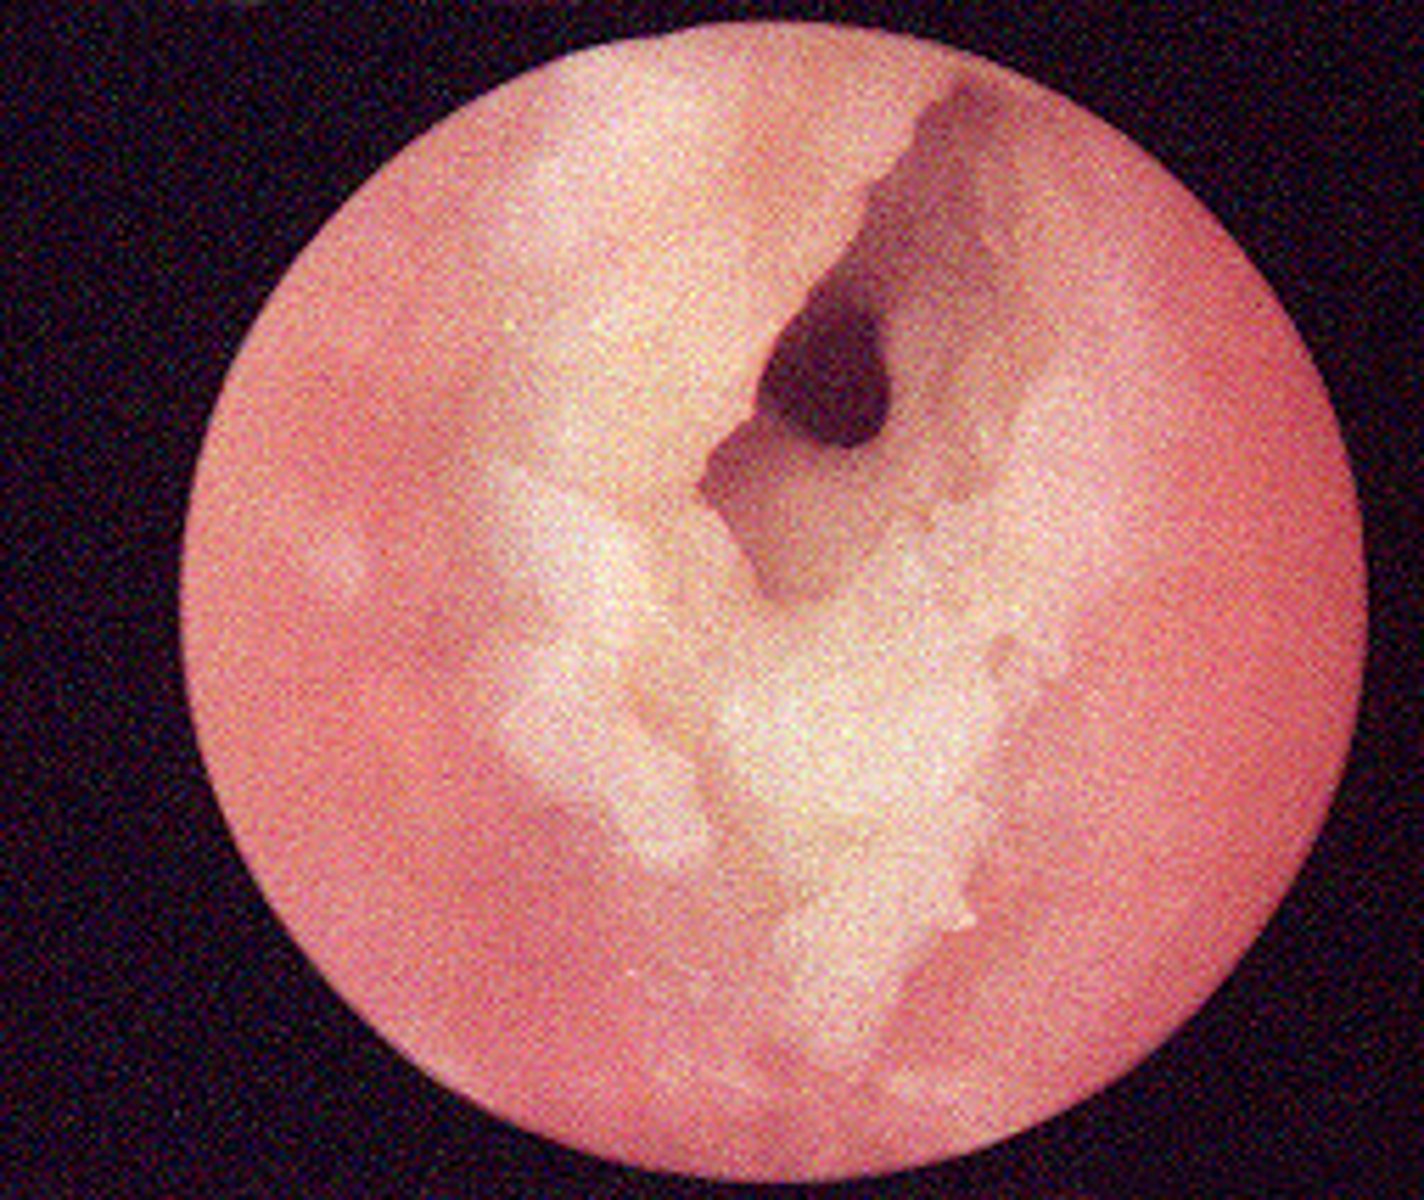

Cerumen impaction

plug of ear wax

<p>plug of ear wax</p>